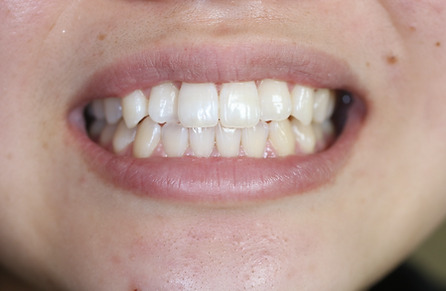

2ホワイトニング【治療例1】

治療前

治療後